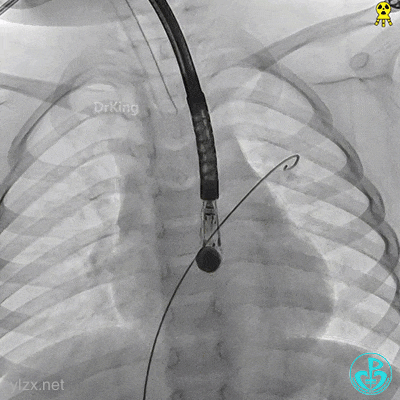

锁定前确认

牵拉试验,封堵器骑跨于缺损两侧。

封堵器整体稳定,仅右盘随钢缆牵拉移动。

封堵器锁定

锁定后,主动脉短轴切面显示封堵器呈Y字型抱住主动脉根部。

牵拉稳定,锁定成功。

牵拉试验,封堵器位置固定,未见明显位移及形变。